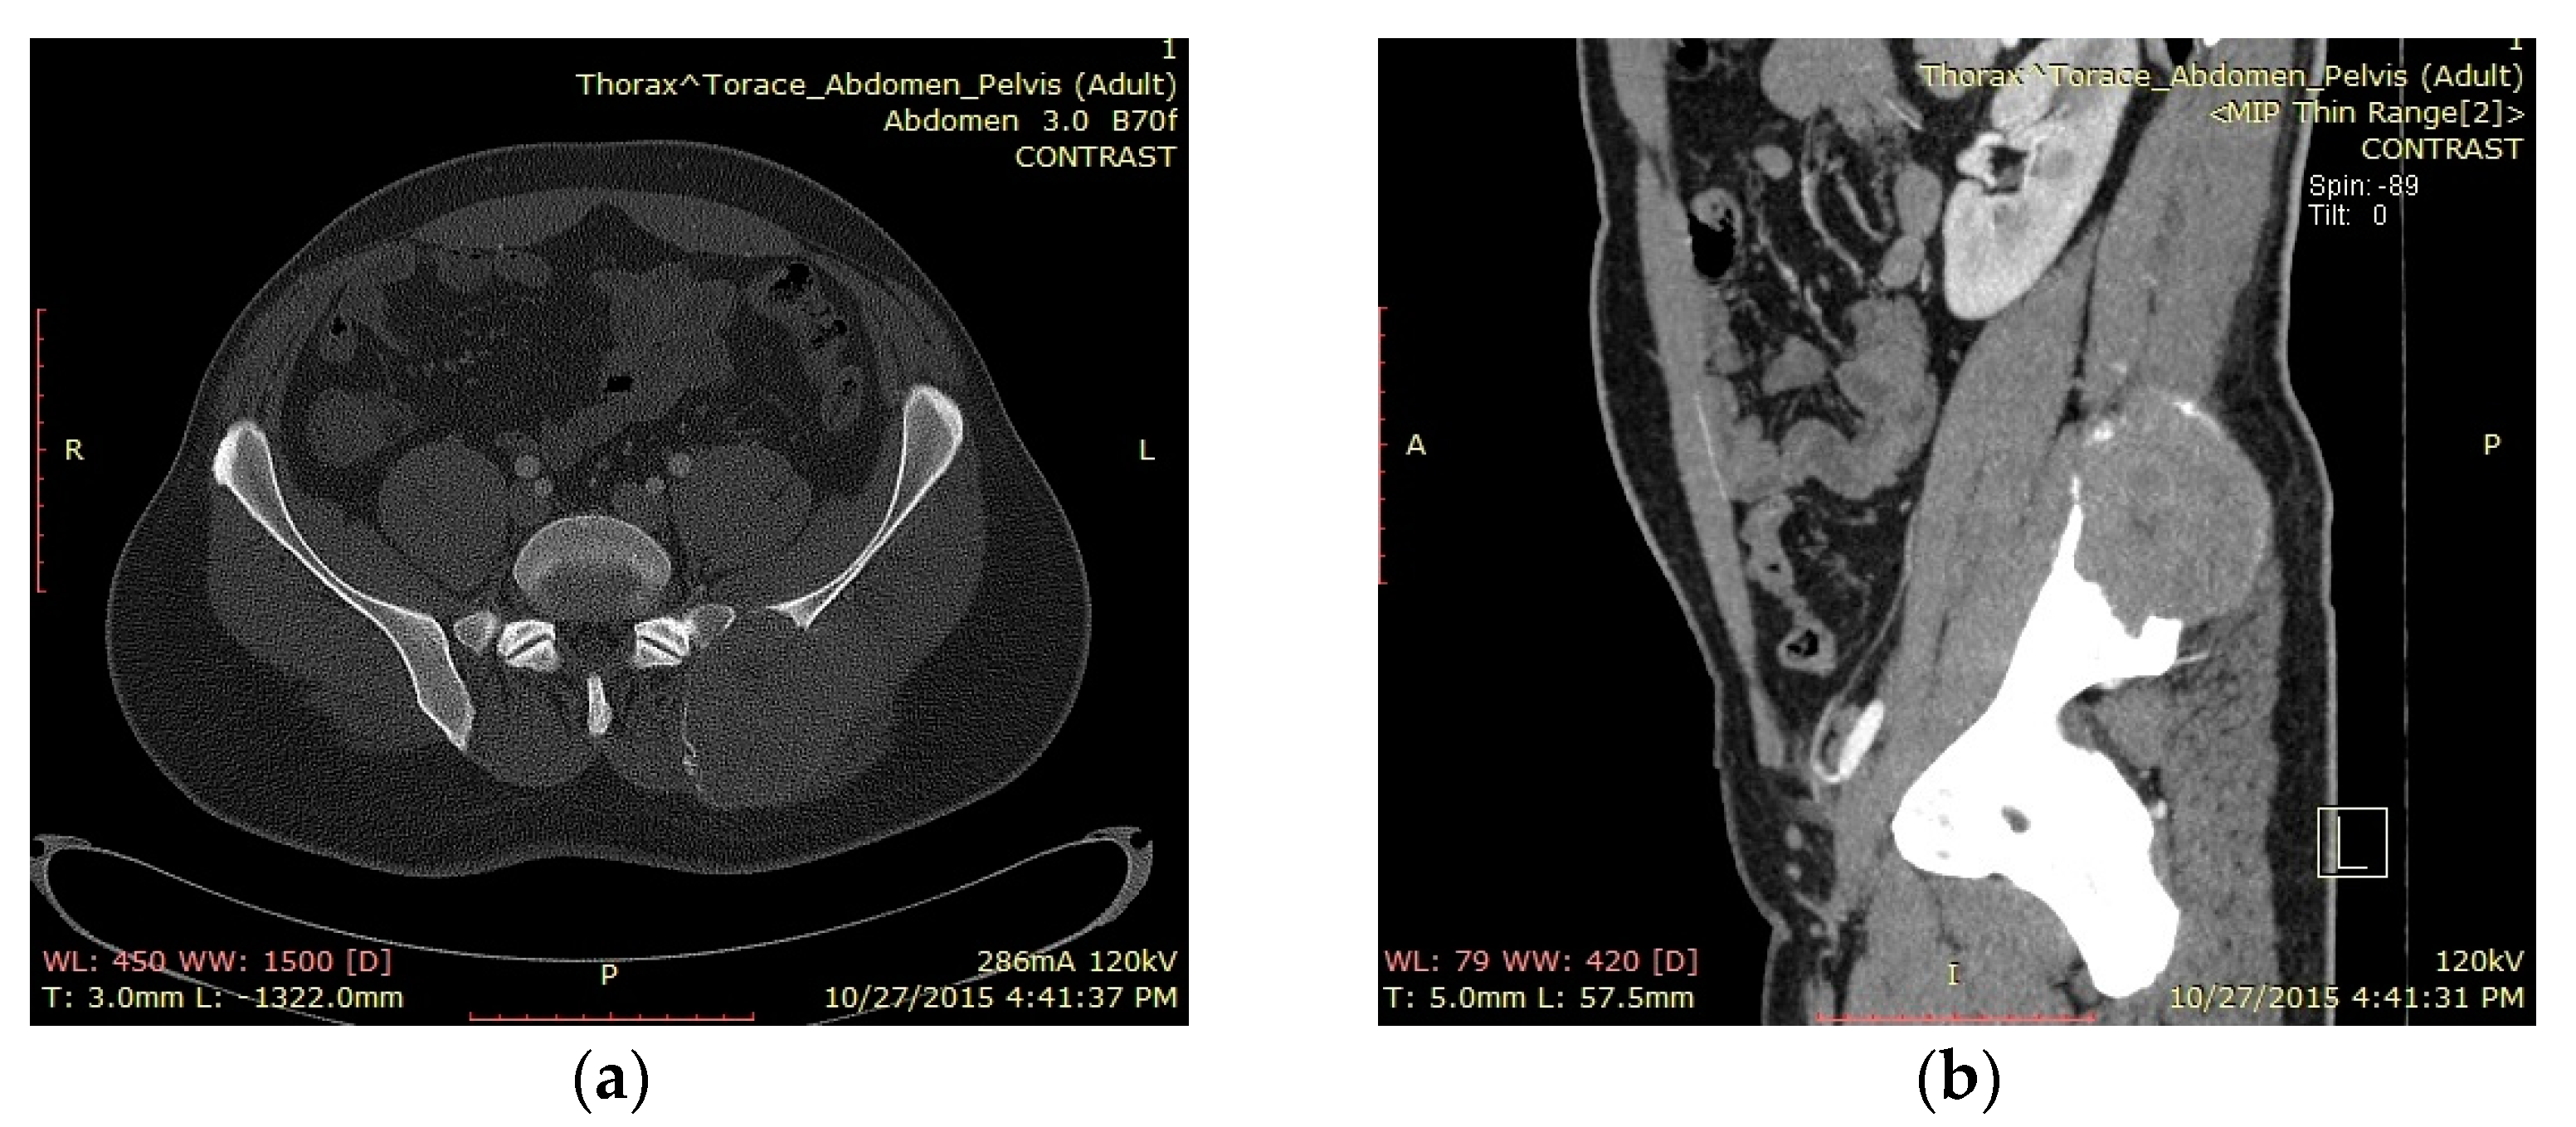

3.3. Case 3